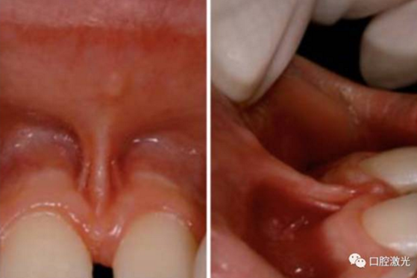

通過臨床檢查,發(fā)現(xiàn)上唇系帶已延伸通過上前切牙中間牙齦部位進入到上頜腭側(cè),導(dǎo)致上切牙間空隙最大處5mm、最小處4mm。整個手術(shù)過程耗時8分鐘。由于本例中系帶組織較厚、在牙齦內(nèi)較深并且已經(jīng)貫穿進入內(nèi)部腭側(cè),因此采用了表麻加局部麻醉,而大多數(shù)系帶整形手術(shù)僅采用表麻即可。

首先沿系帶兩側(cè)靠近牙齦位置的邊緣處做V型切開。在利用激光進行軟組織切割時,可以用手或工具將唇部系帶拉緊。然后沿菱形方向,由外朝里進行切割,去除過于的組織和纖維。必要時,可以對腭側(cè)和切牙間牙齦部位的系帶纖維組織進行切割或氣化消融。整個手術(shù)過程少量流血或不流血,視野清晰、便于快速操作。術(shù)后無需縫合,僅用脫脂棉壓迫30秒即可。由于手術(shù)迅速,患者的配合度很高。

一天后復(fù)診可以看到恢復(fù)情況良好,沒有水腫和疼痛發(fā)生。4個月后,相比治療前,前牙間距縮小了1.5mm,可以繼續(xù)進行正畸治療。

術(shù)后1天

術(shù)后4個月